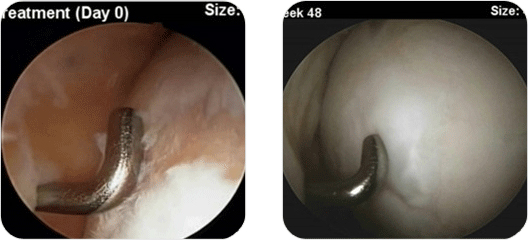

관절 줄기세포 치료는 제대혈에서 추출한 간엽줄기세포를 분리 배양한 줄기세포치료로 100% 순수한 간엽줄기세포로 구성되어 있어 연골손상부위의 크기나 연령의 제한이 없다는 것을 최대 장점으로 꼽을 수 있습니다. 기존의 세포치료는 자가연골세포나 골수세포였으므로 분화능력에 제한이 있어 젊은 연령층(50대 미만)에만 제한적으로 적용 가능할 뿐이었습니다.

그러나 줄기세포 치료제인 카티스템은 50대 이상의 슬관절염 환자에서 뛰어난 효과를 보인 바 있습니다. 또한 임상에 참여한 환자 대부분(88.4%)에게서 재생된 연골이 손상 전 연골과 유사한 연골임이 확인되었는데, 재생된 연골이 손상연골과 유사한 연골, 즉 hyaline-like 연골이 아닌 경우에는 일반적으로 2~3년을 넘기지 못하고 재치료를 받게 되는 경우가 대부분입니다.

관절 줄기세포 연골재생 수술은 일반적인 관절경 이후에 슬개건 좌측을 약 4~5cm만 미니절개하여, 내측대퇴과의 연골결손부위를 노출시킨 후 그 상태에서 젤 같은 형태의 줄기세포 치료제인 카티스템을 결손부위에 뿌려서 모양을 잡아주는 간단한 수술입니다.

최소절개하는 이유는 관절경상 흐르는 물이 있으면, 젤 상태의 줄기세포 치료제를 잘 굳히고 모양을 잡아주기 어렵기 때문입니다. 줄기세포 치료의 개념이 아직 잘 잡히지 않아서 복용하는 약이나, 혹은 주사로 되어 무릎부위에 주사하는 제형으로 아는 분들이 있는데 줄기세포 치료제는 성체줄기세포의 배양액을 연골세포로 만든 젤형태의 연골결손치료제입니다.